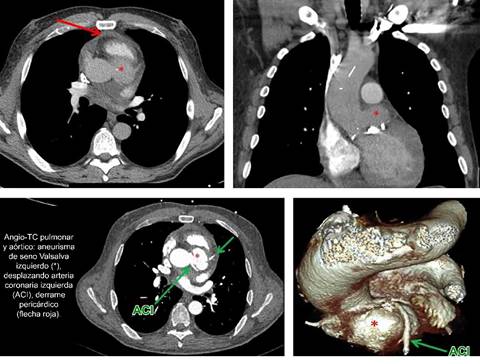

El estudio fue negativo para TEP, pero reveló la presencia de un discreto derrame pericárdico y una válvula aórtica severamente calcificada con alteración morfológica de la raíz aórtica, en la que se identificaba una imagen ovalada parcialmente calcificada en su margen basal en íntima relación con el seno coronario izquierdo, que sugería corresponder con un aneurisma del mismo, de aproximadamente 23 mm de diámetro máximo.

Ante los hallazgos y tras valoración del paciente por Servicio de Cardiología y realización de ecocardiografía reglada, se completó el estudio con una angio-TC de aorta torácica con sincronización cardiaca, que confirmó la sospecha diagnóstica de aneurisma del seno de Valsalva izquierdo con una válvula aórtica severamente desestructurada y de apariencia bicúspide (Figura 1).